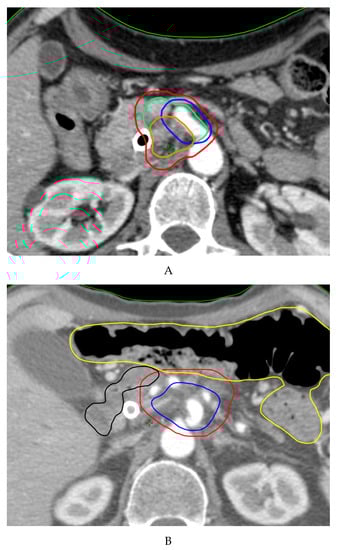

4.1. Conventional Radiotherapy

4.2. Stereotactic Body Radiation Therapy (SBRT)